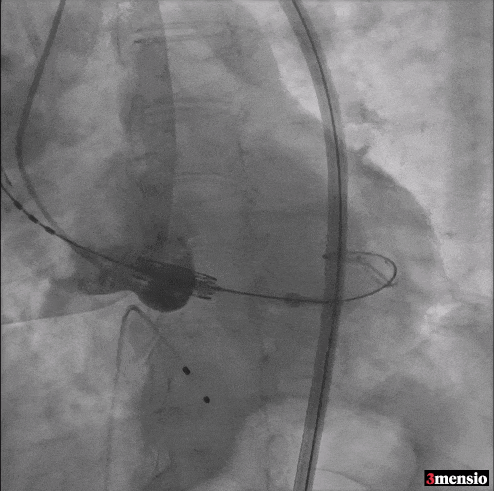

综合考虑患者未来冠脉介入治疗、Redo-TAVR的需求,以及患者横位心和升主动脉扩张的解剖特征,同时患者为融合嵴钙化的Type1 带嵴BAV,拟选用球扩瓣+Downsize的策略。室间隔膜部瘤上缘高度7.2mm,23 S3人工瓣的内裙边高度9.3mm,患者瓣上8mm限制明显,约为23.6mm,拟采用标准容积+2ml、高位释放的人工瓣释放策略。

拟植入Sapien 3 23mm瓣膜(扩张容积+2ml),高位释放

Step 2 瓣膜定位、释放